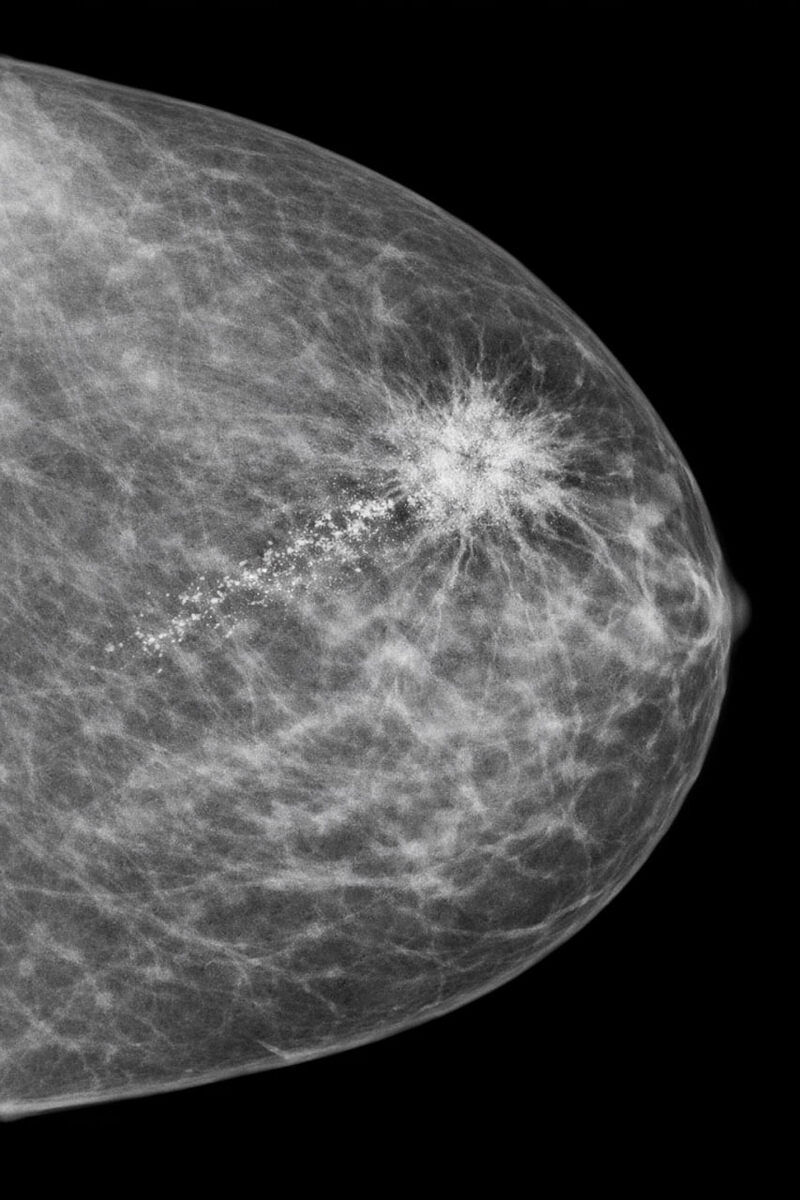

1️⃣ Маммография видит то, что не видите вы

Самообследование — это важно. Но когда вы нащупали узел руками, опухоль уже живет в груди около 8–10 лет. 🔬 Маммография находит проблему, когда она размером меньше горошины. На этой стадии рак излечим в 98% случаев. ✅

8️⃣ Заключение написано страшными словами

📄 Фиброз, кисты, кальцинаты, асимметрия. Не читайте заключение сами. ❌ Не гуглите. 🔍 90% этих «страшных» слов — возрастная норма или доброкачественные изменения. Читать рентген должен онколог или маммолог. 👨‍⚕️